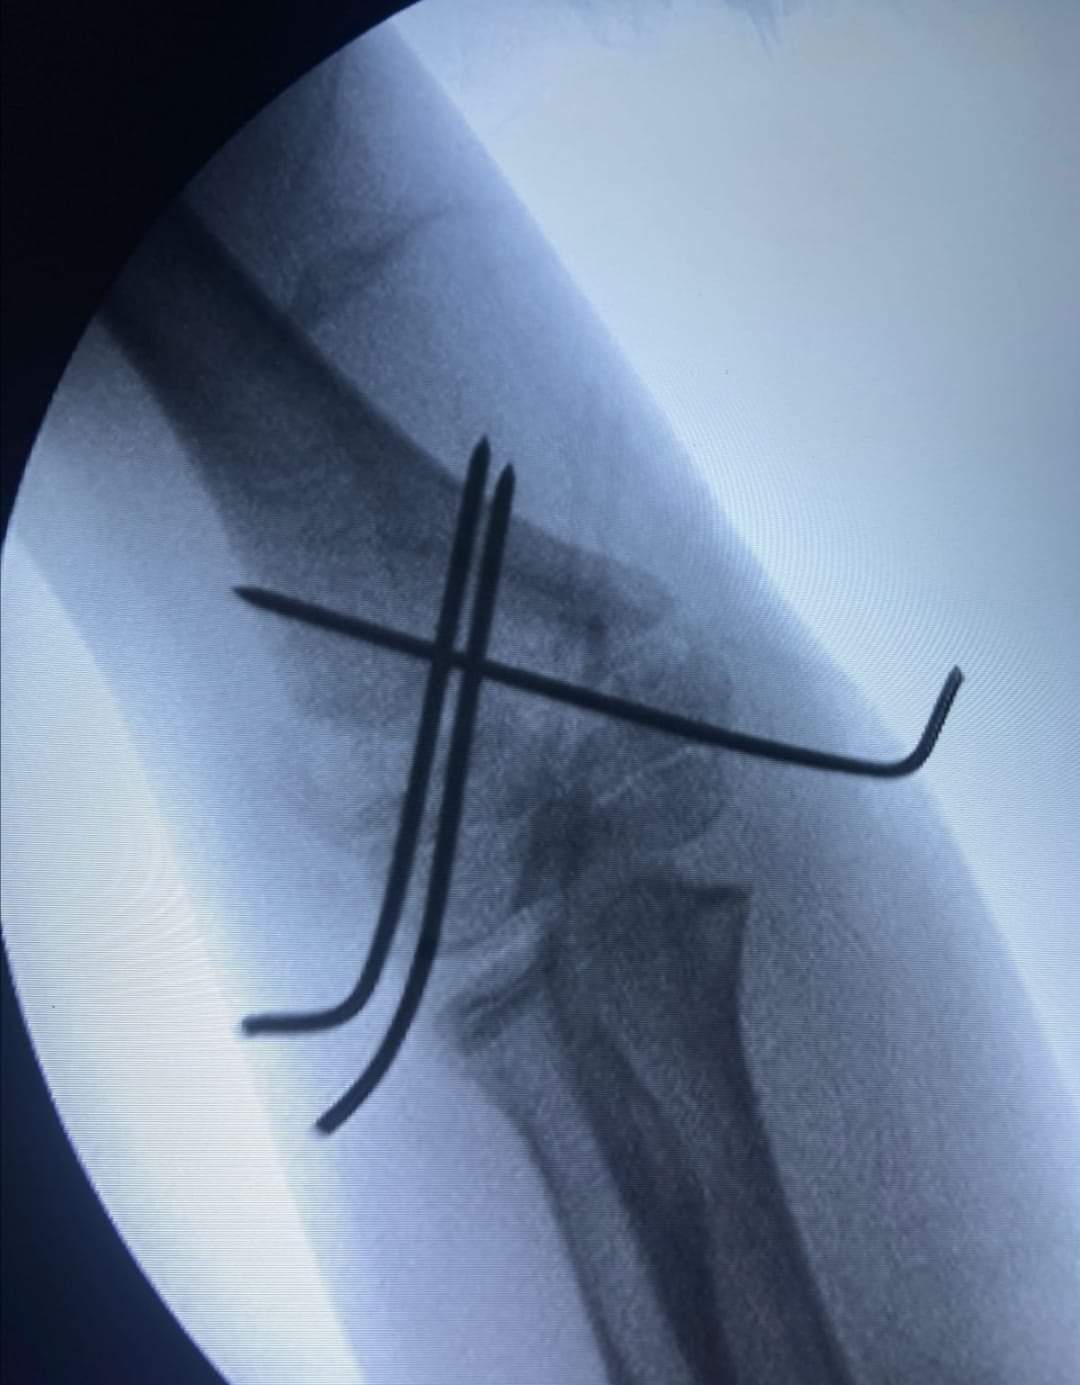

وطنا اليوم -  يقوم بعمليات تثبيت الكسور المعقدة بشكل طاريء وتبديل المفاصل بشكل مبرمج  مما خفف على المواطنين البحث عن أسرة في مستشفيات مركزية رغم صعوبة عمليات العظام من الناحية التقنية في المستشفيات النائية  إضافة الى  استقبال اعداد كبيرة بالعيادات ومعالجة جميع المرضى بالطرق المثلى انه الدكتور الانسان البارع والمتميز يزيد البريزات طبيب العظام في مستشفى الاميرة سلمى / ذيبان عيادة العظام  علماً بأنه كان  مستشفى تحويلي منذ تاسيسه والدكتور البربزات وقبل اربع سنوات في عام 2020  منذ انتقاله للمستشفى يقوم بهذه العمليات ومن بينها  عمليات نوعية لمرضى يعانون من كسور معقدة في الترقوة واجراء عمليات دقيقة ومعقدة لكسور لمرضى في مختلف أنحاء الجسم وعمليات تثبيت الكسور المعقدة وتركيب المفاصل وغيرها الكثير  والديسك " وآلامه وتبعاته وعلاجه وإجراء عمليات معقده وصعبه.

وأجرى الدكتور البريزات عمليات كبرى في جراحة العظام والتي تحتاج إلى مراكز متقدمة ومتطورة. وكذلك العمل على تثبيت أغلب انواع الكسور بطريقة طارئة وتبديل المفاصل بطريقة مبرمجة بما يتناسب مع امكانات المستشفى والتي هي  جزء من  العمليات الدورية بمستشفى الاميرة سلمى في ذيبان  والتي تخفف العبئ على المستشفيات المركزية وعلى المواطن في آن واحد.

وعبر كثير من  المرضى وذويهم عن عظيم شكر هم وامتنانهم للدكتور البريزات على ما بذله ويبذله  من جهود كبيرة واستثنائية في تعامله مع المرضى والمراجعين  ومتابعته الحثيثة لهم والاطمئنان عليهم والتي تكللت جميعها بالنجاح وله الدور الكبير   برفع كفاءة قسم العظام  بالمستشفى بشكل عام والذي  أصبح  متطوراً بالقيام بالعمليات مثل تثبيت الكسور المعقدة و تركيب المفاصل و غيرها.